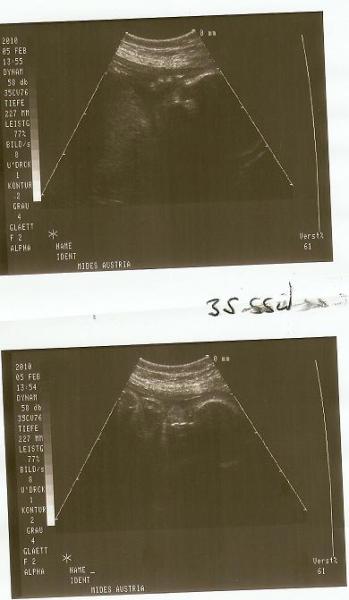

war ja grad beim fa .. die wehen sind da ..auch "regelmäßig" also alle 2-8 minuten auf dem ctg .. aber sie müssen noch stärker werden... hab noch ne dosis magnesium verschrieben bekommen und viiiel ruhe .. soll ja wenn möglich erst ende feb kommen. fundusstand diesmal 4/N gewicht der kleinen ca 2300 gramm ... bissi leicht aber noch in der norm. hab diesmal 2 fotos bekommen .. aber da sieht man ned viel ... da sie schon tief im becken sitzt. Hab schon den einweisungsschein fürs kh bekommen. hm hab ich sonst noch was vergessen? ne glaub nicht .. also dann mal sehen wie lange das noch gut geht.

Bild zu